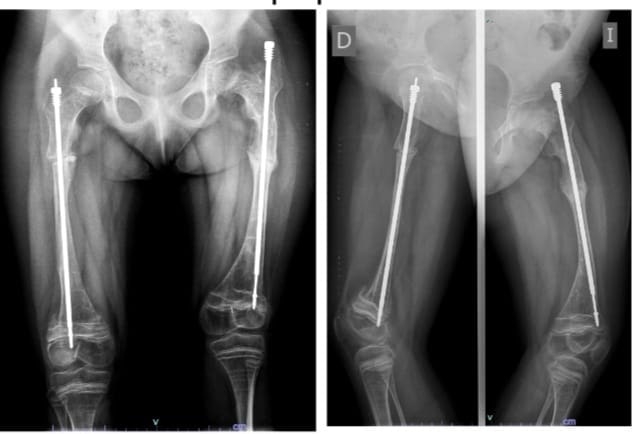

“Vino en un coche de bebé y se le práctico un tratamiento con un clavo especial, un clavo telescopado para corregir la deformidad, que se ancla en zonas seguras del hueso. Se calcula dónde tiene que ir cierto corte del hueso para recuperar el eje normal del cuerpo. El chico crece con el clavo y el clavo se elonga a medida que el chico crece”, describió.

De este modo el niño o la niña crece sin el peligro de fractura y no se genera una deformidad constante que es lo que le genera la falta de movilidad y el dolor.

Es importante, no obstante, el control permanente del clavo telescopado “hasta que cumpla la mayoría de edad ósea, cuando termina el crecimiento, que varía entre el hombre y la mujer”, subrayó Garabito.

El tratamiento de la pequeña tuvo una duración de 5 años en donde el especialista comenzó con la corrección del eje de la deformidad para luego colocar en los fémures los clavos telescopados. “Por suerte el cuerpo reacciono perfectamente, ahora vamos a comenzar los ciclos de rehabilitación despacito, pero estamos muy contentos”.

“En el rango de los 11 hasta los 13 años el índice de fractura, con el tratamiento colocado, disminuye un 60% o 70 %, pero es importante que se los proteja desde que se detecta la patología hasta que concluye su maduración”, aclaró.